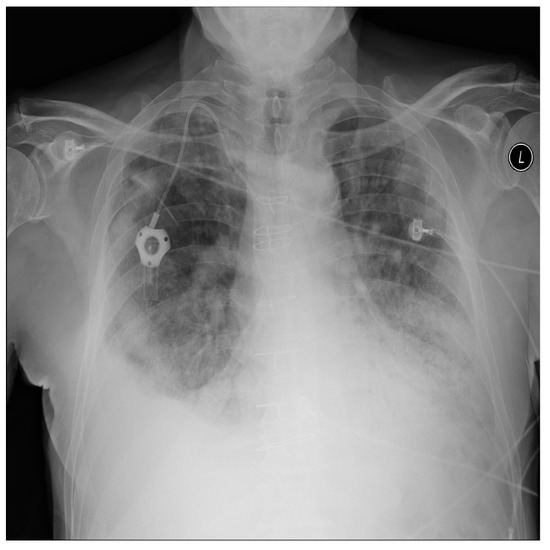

For a more intuitive understanding, we visualize a sample of each category in Figure 9, Figure 10 and Figure 11.

Figure 9. Covid sample: X-ray Image dataset.

Applsci 13 00454 g009